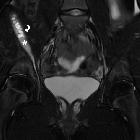

Subperiosteal

hematoma of the ilium: an unusual complication of acetabular fracture. The “iliac wing sign” consists of linear edema-like signal at the iliacus muscle attachment entering the iliac wing (arrows). This should be differentiated from subperiosteal iliac hematoma as they often share a common clinical presentation.